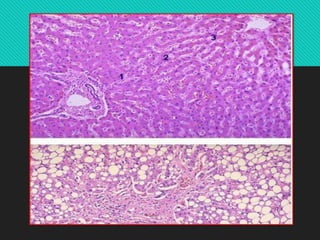

 Microscopy:

 Central veins and sinusoids are distended with blood.

 Centrilobular hepatocytes shows degeneration and atrophy

 Central hemorrhagic necrosis

 Peripheral hepatocytes shows fatty change.